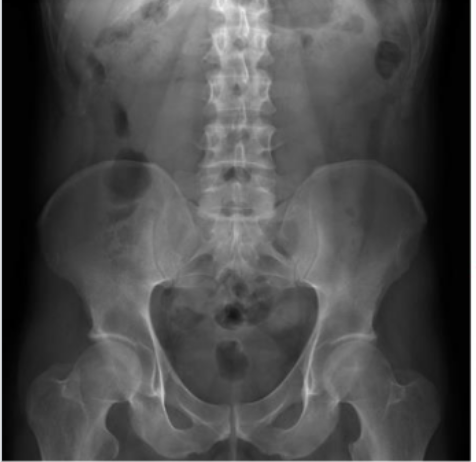

Identify Psoas muscles, lumbar vertebrae, femur, illiacus

yes